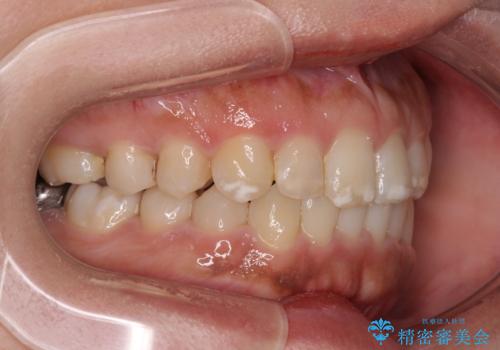

- 上下前歯の叢生を気にして来院された患者様です。

軽度な叢生であり、安価で短期間の治療を規模されていたため、インビザライン・モデレートを用いて矯正治療を行うこととしました。

インビザライン・モデレートは、製作できるアライナーの枚数に制限があるため、移動可能な量に限りがあるものの、インビザライン・ライトよりも枚数が多いため、幅広い症例に対応可能です。